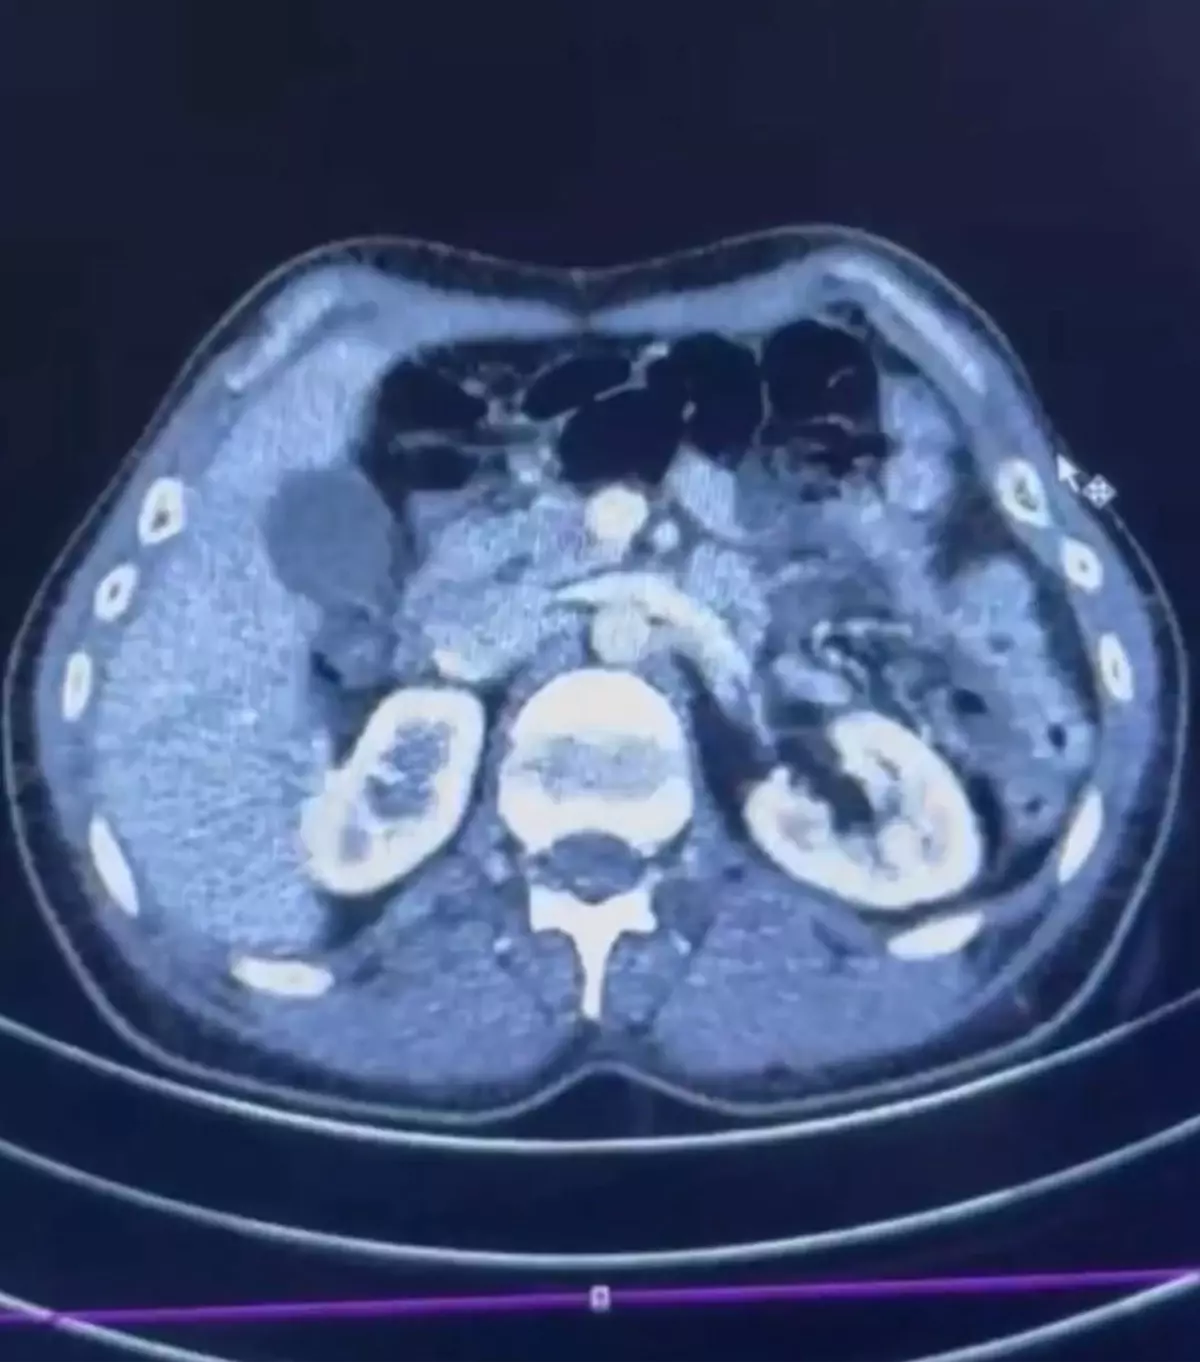

İl Emniyet Müdürlüğü Narkotik Suçlarla Mücadele Şube Müdürlüğü ekipleri, uyuşturucu ticareti yapan kuryelerin yakalanmasına yönelik çalışma başlattı. İran uyruklu 3 şüphelinin yurt dışından Türkiye'ye uyuşturucu getireceği bilgisi alındı. Şüphelilerin bulunduğu adreslere düzenlenen operasyonla S.C. (41), G.M. (28) ve R.B.C. (35) gözaltına alındı. Şüphelilerden S.C. ve R.B.C. muayene edilmek üzere Kayseri Şehir Hastanesi'ne getirildi. Röntgeni ve ultrason çekilen şüphelilerin midesinde yaklaşık 50 kapsülde 554 gram uyuşturucu olduğu tespit edildi. Uyuşturucular sağlık ekiplerinin tedavisiyle çıkarıldı. 3 şüphelinin emniyetteki işlemleri ise sürüyor.